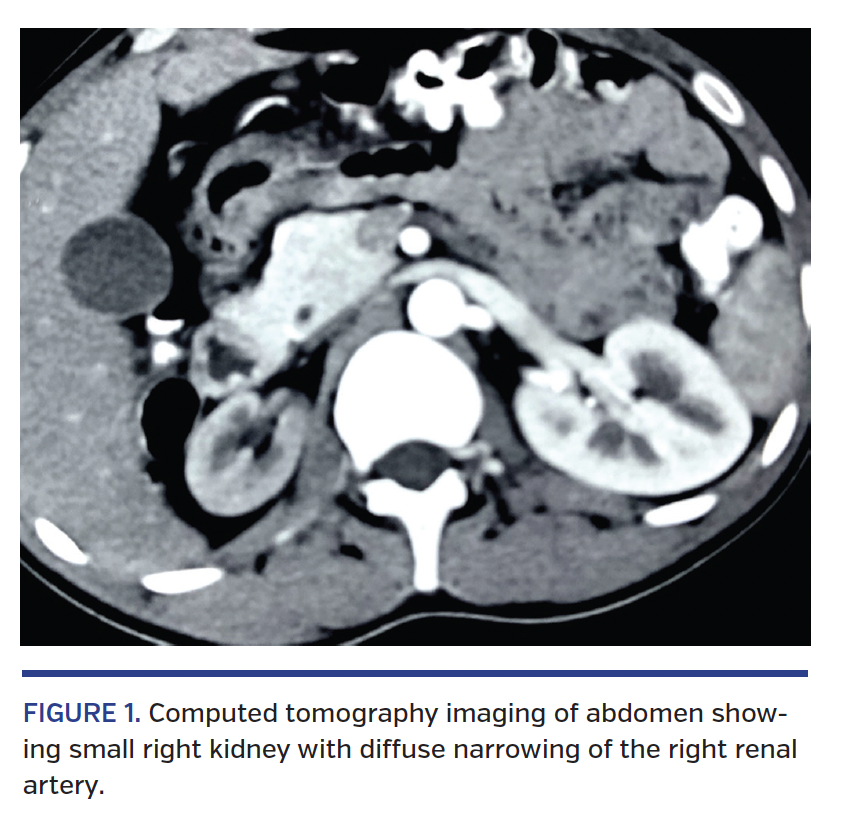

From ct.medicinetoday.com.au

Renal artery stenosis and hypertension when to screen and how to treat Renal Artery Stents Atherosclerotic renovascular disease remains highly prevalent and. procedures to treat renal artery stenosis may include: It’s usually the result of. renal artery stenosis is the narrowing of one or more arteries that carry blood to your kidneys (renal arteries). renal artery stenosis (ras) may result in resistant (refractory) hypertension (htn), progressive decline in renal function, and cardiac. Renal Artery Stents.